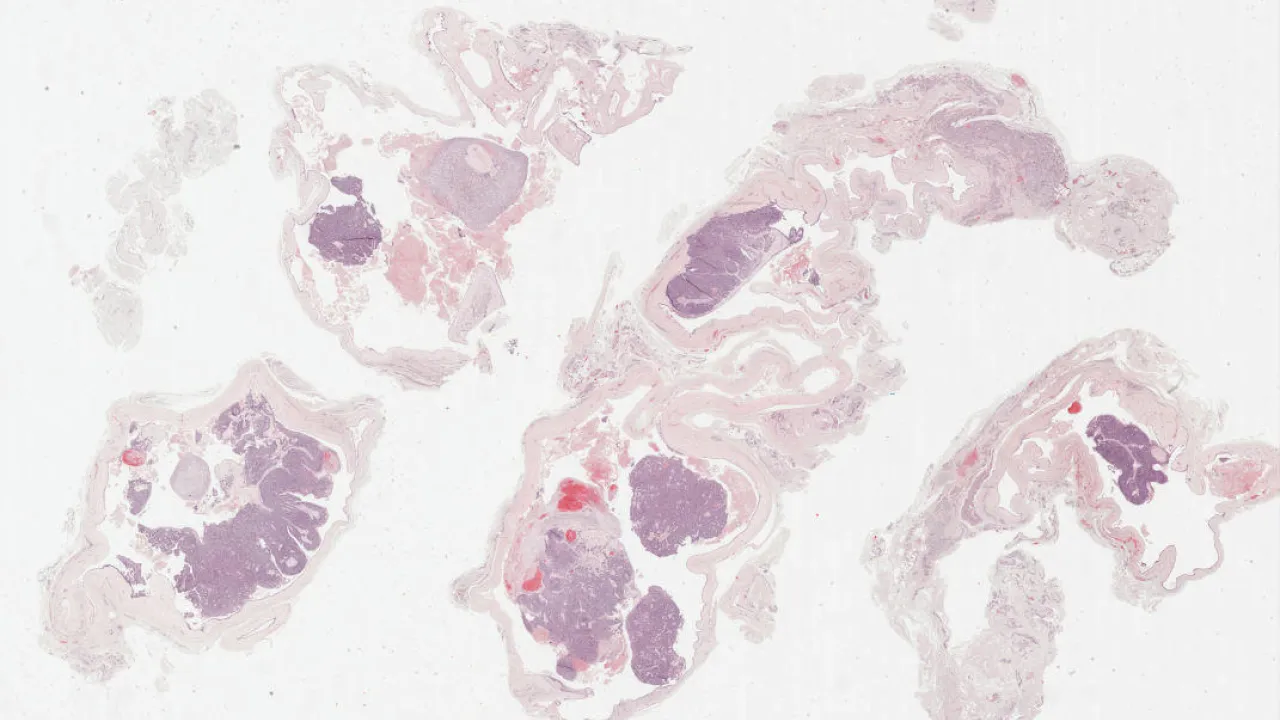

Abdomen, OEIS Complex

Bladder, OEIS Complex